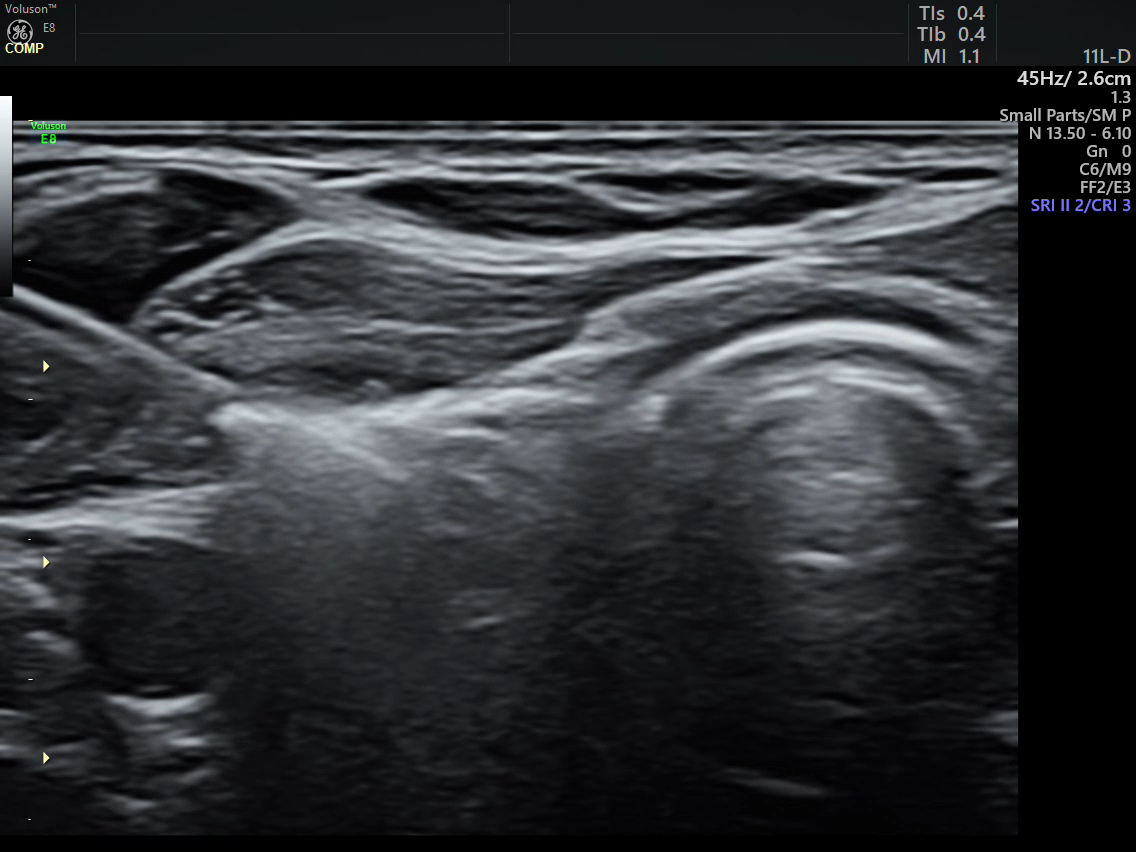

该患者为年轻男性,因当地体检发现骨密度减低,随即到西安、北京多家大型三甲医院复查,发现甲状旁腺激素及血钙水平异常升高,超声检查提示左侧甲状旁腺占位。因多方了解我院超声医学科可以射频消融治疗,为求精准诊治慕名前往我院陆港院区超声医学科求治。我科魏炜副主任在详细了解该患者既往临床资料后对其进行了超声检查,发现该患者左侧下部甲状旁腺内可见一大小5.1x5.2x13.2mm低回声结节,边界清,形态规则,内回声欠均匀,CDFI:结节内部可见丰富血流信号;余甲状旁腺形态、大小未见异常。患者甲状旁腺素158pg/ml(正常参考范围15-65pg/mL),血钙2.89mmol/L(正常参考范围2.11—2.52mmol/L),魏炜副教授根据该患者超声图像特征结合实验室检查明确诊断该患者为原发性左侧下部甲状旁腺功能亢进(甲状旁腺腺瘤),符合射频消融指征。魏炜副主任为患者详细讲解了治疗目的、步骤及可能发生的并发症后,患者决定采取该微创治疗方式。在日间诊疗中心的支持下,患者顺利住院并完善术前检查。

治疗前病灶血流丰富 治疗后病灶血流消失